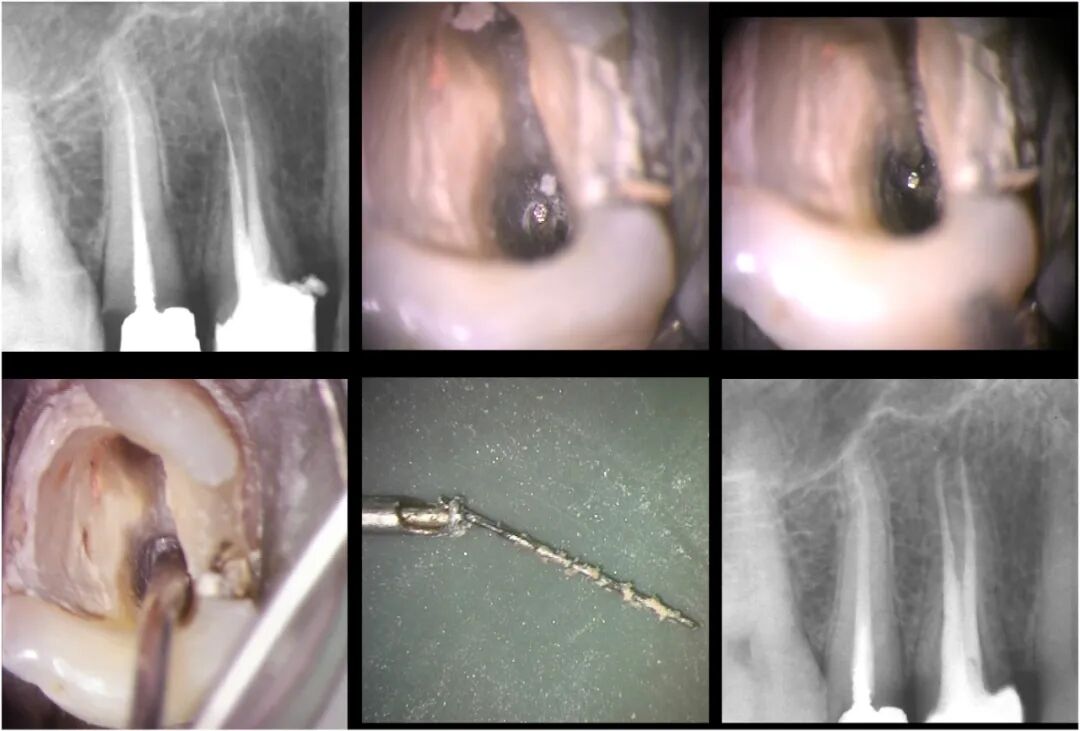

图7. 一例临床病例,从第一前磨牙的直根管中取出分离器械。